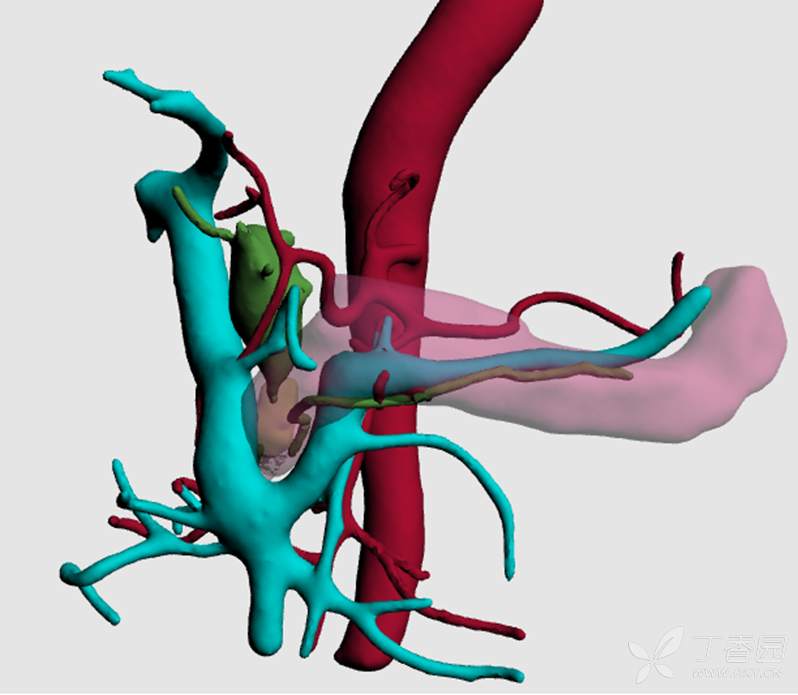

手术开始进展顺利,离断十二指肠后蒙了,因为门静脉前方没有胰腺!(如下图)难道是胰颈菲薄,和幽门一块断了?术中再次阅片,发现胰头确实从门脉后方进入了十二指肠。读到这,各位可以再次仔细看术前CT,门静脉处在十二指肠降部和胰头之间!3D重建可以更直观的展现该患者的第三怪。